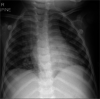

Child with tuberculous meningitis and COVID-19 coinfection complicated by extensive cerebral sinus venous thrombosis

We herein report a case of a child with tuberculous meningitis and COVID-19 coinfection complicated by hydrocephalus, arterial ischaemic stroke and extensive cerebral sinus venous thrombosis. Both conditions induce a proinflammatory cytokine drive resulting, among others, in a prothrombotic state. The disruption of the coagulation system in this case was supported by elevated D-dimers, fibrinogen and ferritin levels, consistent with thrombotic complications reported in some adult patients infected with COVID-19. The child also exhibited prolonged viral shedding that suggests severe disease.